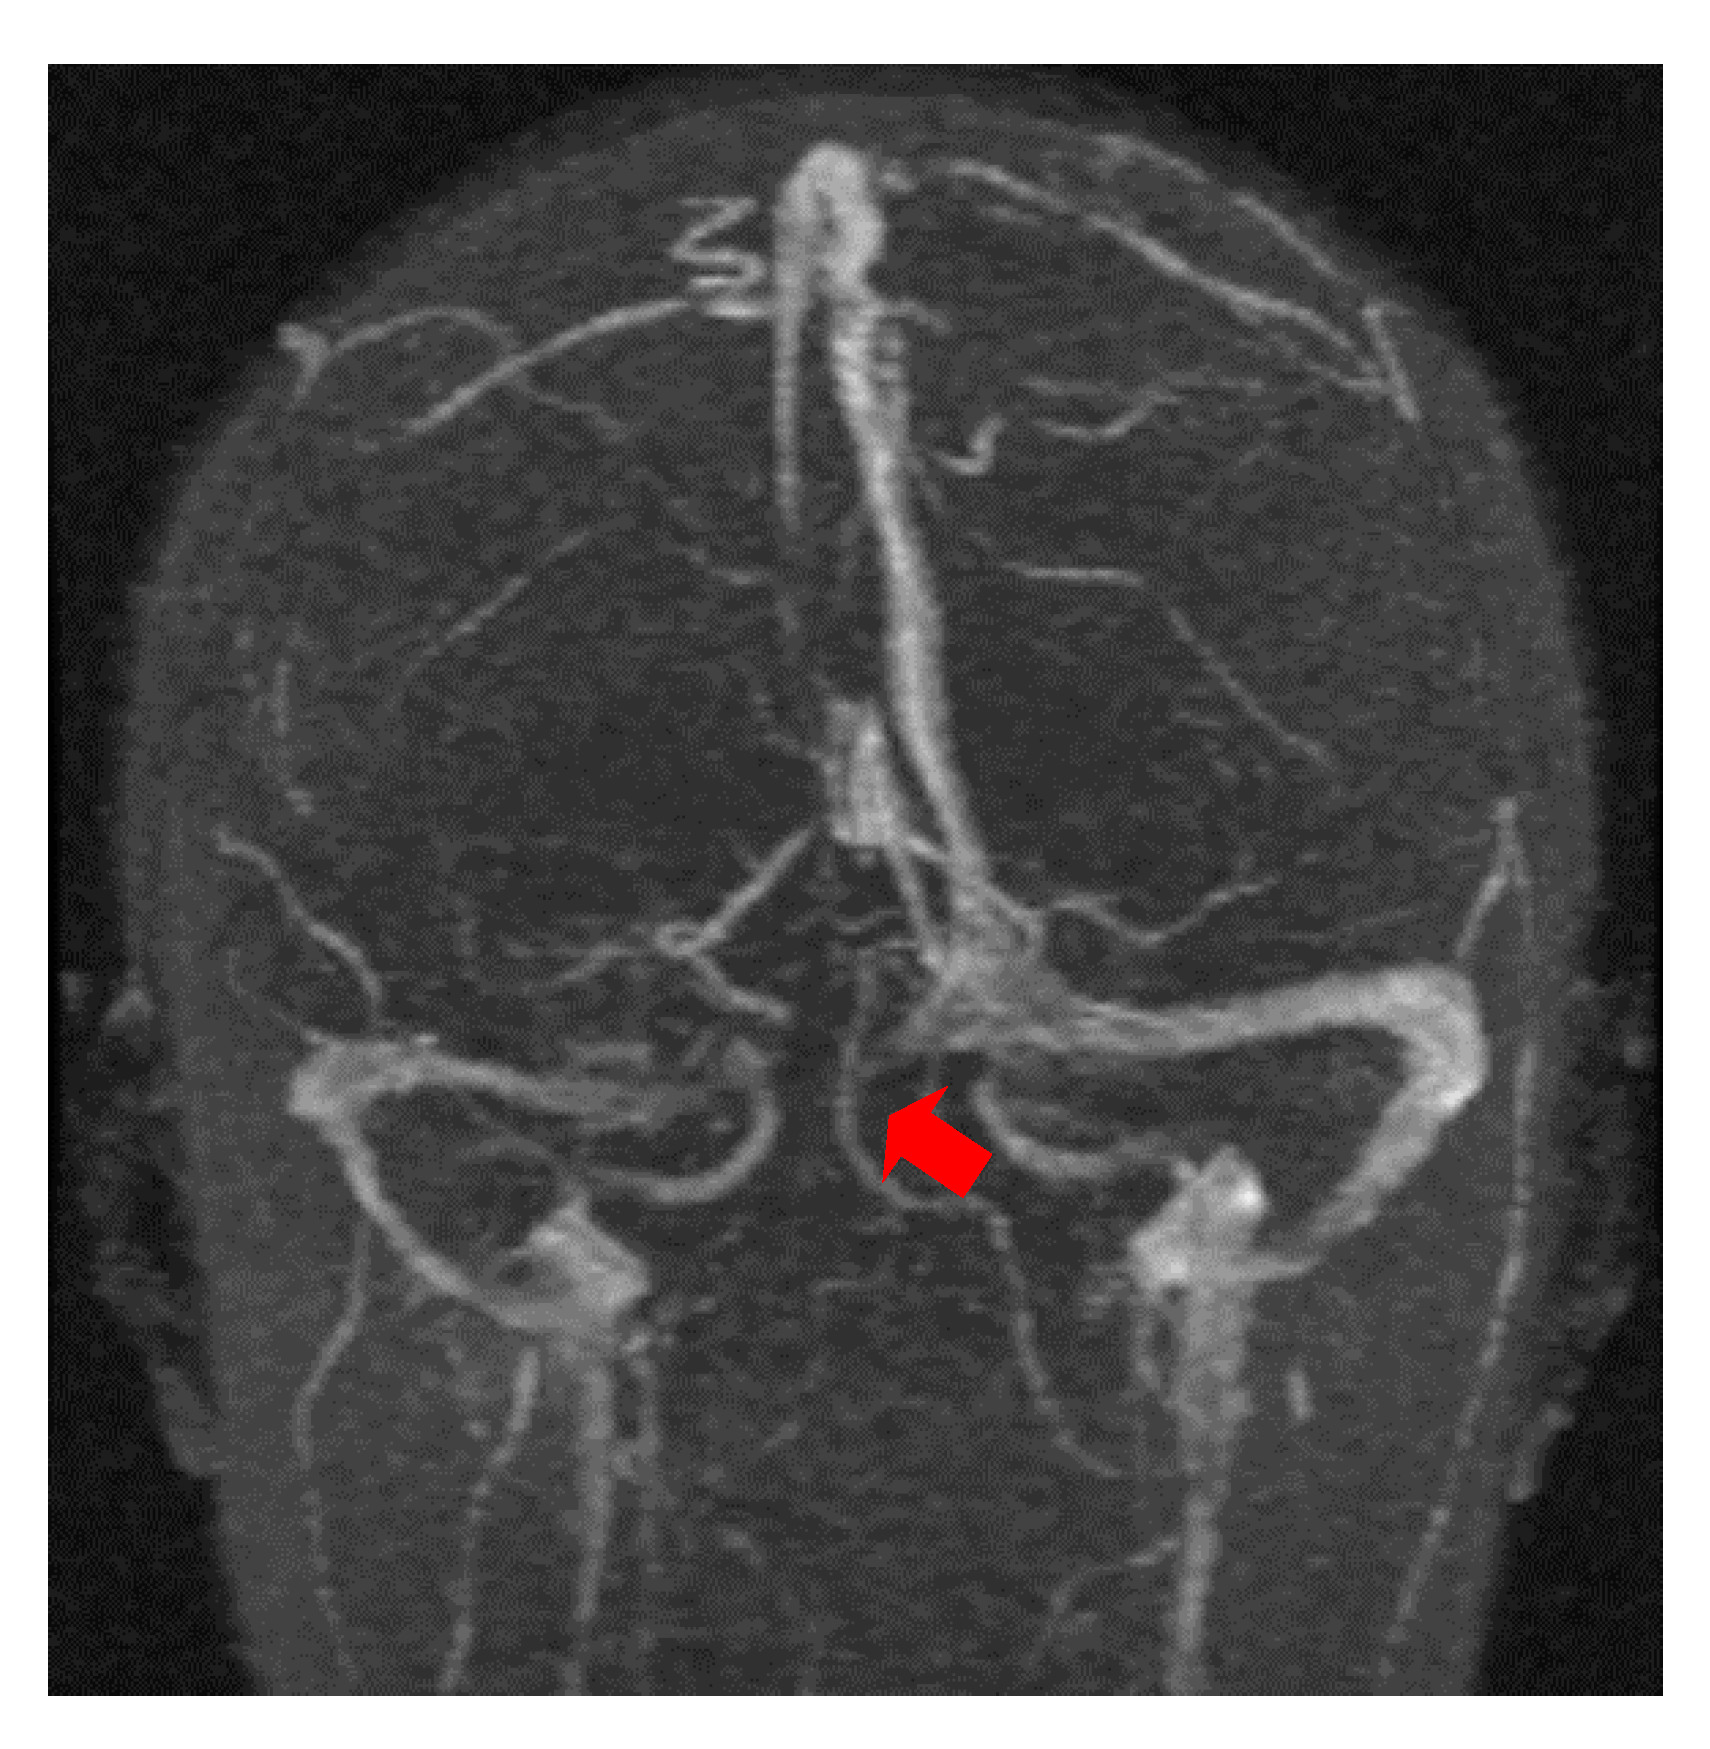

The second case was a female, 31 years old, with an etiology of thrombophlebitis accentuated by the presence of the MTHFR C677T gene polymorphism- homozygous phenotype. The patient was hospitalized with superficial coma, generalized seizures and left hemiparesis. In the course of evolution, subsequent to the cerebral post thrombotic syndrome and edematous encephalopathy, the patient presented symptomatology characterized by generalized seizures under anticonvulsivant treatment and also psychical disturbances (irritability, aggressiveness). The patient was clinically and neuroimagistic assessed after six month and six years from the onset of the disease. The image features can be seen in Figure 3, Figure 4 and Figure 5.

Figure 4. MR- venography 3D- TOF (time of flight) reveals subarachnoid hemorrhage which accompanies superior sagittal sinus and right lateral sinus thrombophlebitis.